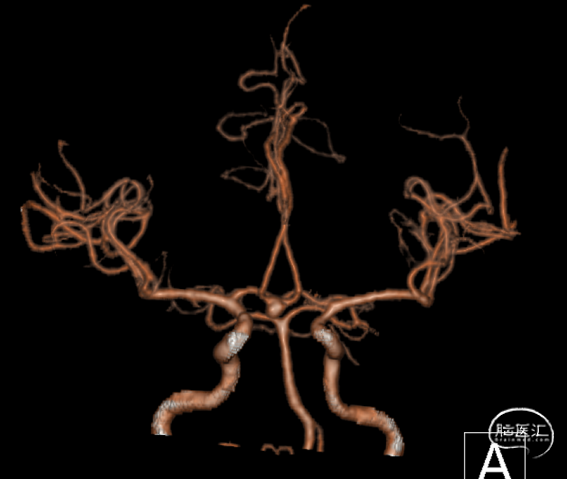

➢ 术前CT及CTA

蛛网膜下腔出血;

前交通动脉瘤。

➢ DSA

右侧颈内动脉血流通畅,前交通动脉可见相对宽颈动脉瘤,大小约3.69*5.18mm,瘤颈宽3.66mm,瘤体上可见两个突起,大脑前动脉及大脑中动脉血流通畅;

左侧颈内动脉血流通畅,大脑前动脉及大脑中动脉血流通畅;

左椎动脉、基底动脉及双侧大脑后动脉通畅。

右侧3D